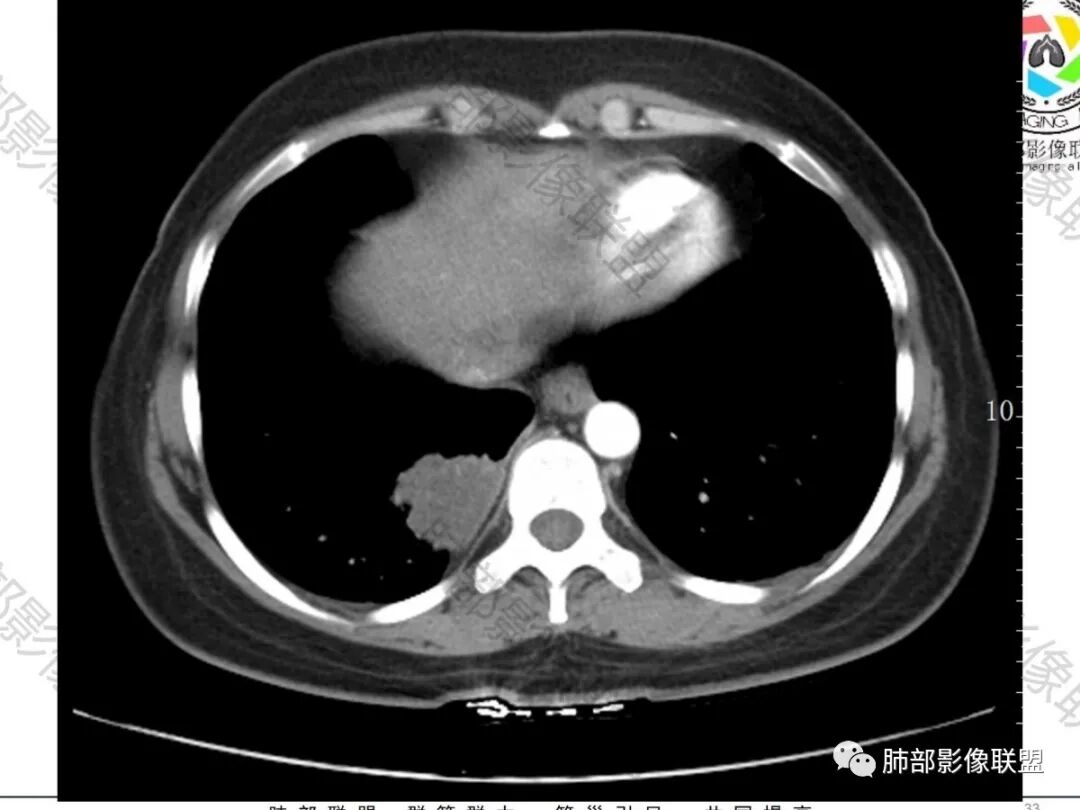

2.右肺下叶脊柱旁类椭圆形块影,边界清楚,密度偏低,隐约见轻度强化囊壁样结构,均匀一致,中央区域未见强化,因属囊样块影。前外缘处显示“壁外”小范围轻度强化软组织密度影,未见磨玻璃晕。

3.块影边缘见匍行血管影,未显示体循环供血。病灶与支气管关系未能显示或呈现。

病灶相邻胸膜轻度强化,未见壁层胸膜侵入或突破。

1.肺部囊样结节影,壁较均匀一致,未见强化(壁轻度强化),常见者为支气管囊肿。内容物可为气体、低密度液体、高密度液体(如伴出血或感染等)。